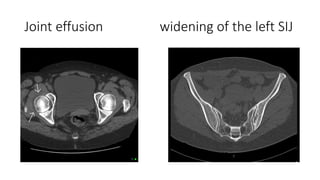

Computed tomography

• Computed tomography (CT) obtains cross-sectional images of skeletal

structures.

• In a patient with a painful joint, CT is most useful for the following

applications:

• Assessing trauma of the spine and pelvis

• Evaluating arthritis in axial joints (eg, sacroiliac, atlantoaxial, and

sternoclavicular)

• Evaluating pain in complex joints in which overlying structures obscure

plain radiography views (eg, ankle, wrist, and temporomandibular joints)

• Evaluating degenerative disc disease of the spine and possible disc

herniations

Joint effusion widening of the left SIJ